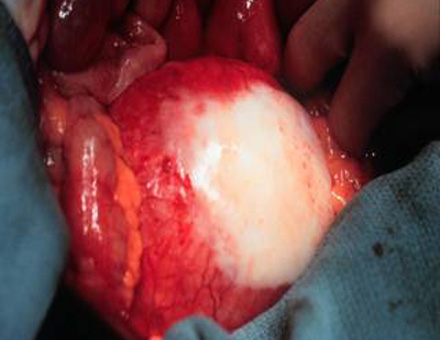

Figure 1 - Operative photograph of a true abdominal aneurysm.

True Aneurysm

A true aneurysm occurs when the inner layers bulge through the outer layer that contains them. Therefore, an aneurysm is surrounded by these inner layers.

An abdominal aortic aneurysm (AAA) (Figure 1) is a common example of a true aneurysm.